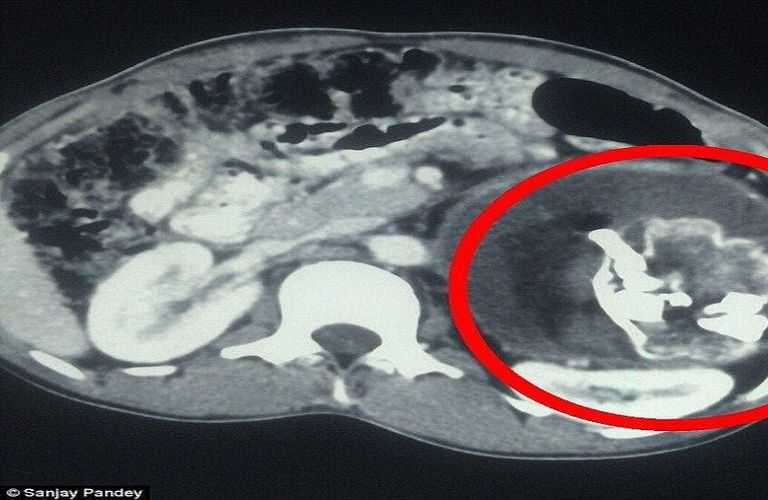

لكن بعد إجراء الفحوصات بالأشعة، اكتشف الأطباء أن التكوين الموجود في تجويف بطن الطفل يحتوي على أنسجة رخوة، ودهون، وسوائل، إضافة إلى بنية عظمية واضحة، مما دفعهم إلى الاشتباه بوجود جنين طفيلي داخل جسده.

كشفت صور الأشعة عن وجود عظام وجه، وعمود فقري، وأضلاع متكونة داخل بطن الطفل، وهو ما أكد تشخيص الحالة النادرة التي تُعرف طبيًا باسم "الجنين داخل الجنين" (Fetus in Fetu)، والتي تحدث عندما يتطور توأم غير مكتمل داخل جسم شقيقه.